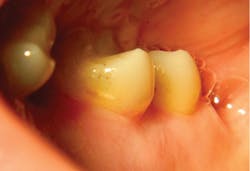

Lastly, it is very important to consider a laser’s water absorption. By providing plenty of water on the tooth surface, we can safely remove hard tooth structure with great visibility and precision. The flip side is that by reducing water supplied at the soft-tissue surface, we are able to sculpt gingival tissue while maintaining coagulation without deep thermal penetration—the laser penetrates only 2.3 microns in soft tissues. This results in a clear surgical field and also enables us to perform subgingival Class V restorations and gingival recontouring in the same appointment, with minimal postoperative discomfort. Restoring difficult clinical scenarios, such as external resorption (figures 6a–6d) is no longer a problem.

Figures 6a–6d: Gingival recontouring and restoration of Class V external resorption lesion in the same appointment